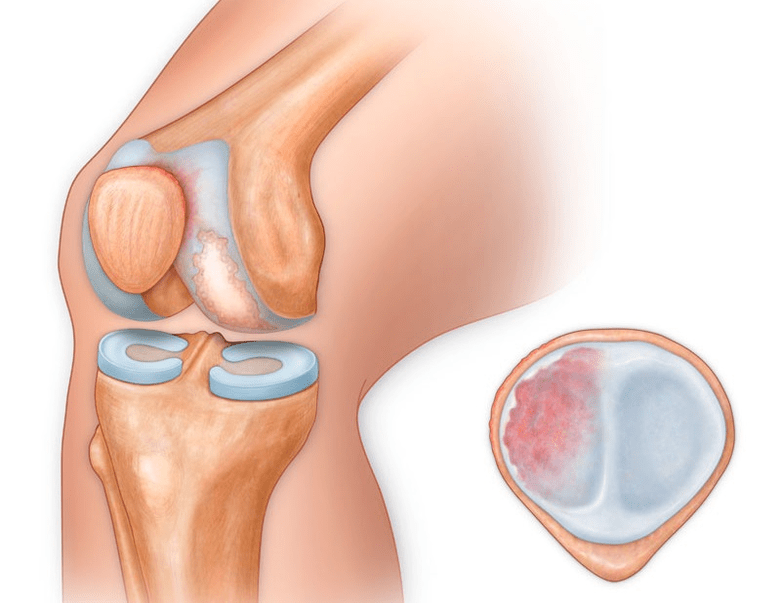

Naast het binnenste of buitenste deel van de knie kan artrose ook de oppervlakken tussen de patella en de intercondylaire groef van het femur aantasten. Deze optie wordt aangeroepen patellofemorale artrose.

De oorzaak is meestal een subluxatie, fractuur of lateralisatie van de patella.

Synovitis

Synovitis van het kniegewricht is een ontsteking van de bekleding van de inwendige holte van het gewricht. De ziekte manifesteert zich in de vorm van zwelling van de knie, roodheid van de huid en beperkte mobiliteit van het gewricht. Met de ontwikkeling van artrose komt synovitis vaker voor, duurt langer en er is een grote hoeveelheid vocht bij betrokken.